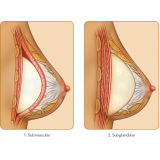

Conheça os procedimentos de excelência para a realização de uma cirurgia plástica a laser!